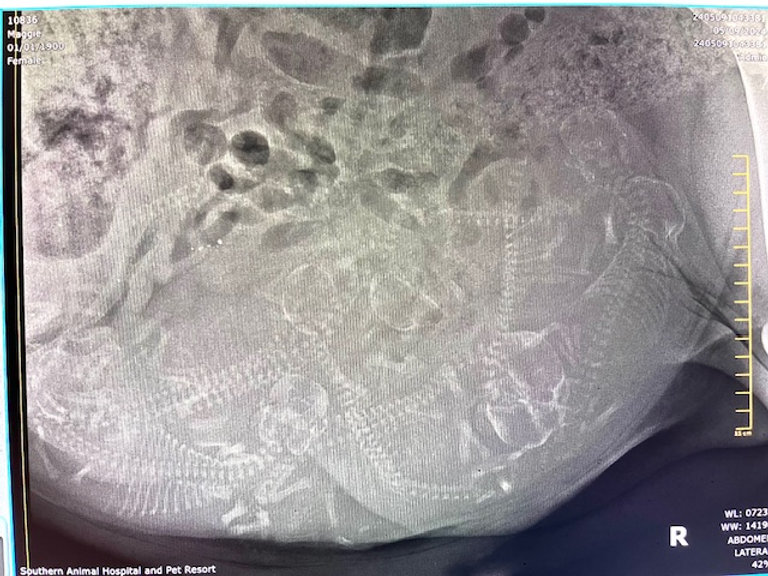

We went for Maggie’s x-ray today and it looks like she has 8-9 puppies 🐾. We are sooo excited for their arrival! Maggie’s due date is next week (May 15th-17th). I will send each of you an email as soon as the puppies arrive. I will also post their pictures here on the blog.

Here is a picture of the x-ray: